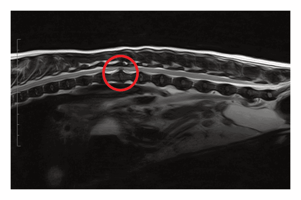

Diagnostic imaging for acute intervertebral disc extrusion in dogs

Dogs sustain acute injuries to the spinal cord for several reasons, including trauma, ischaemic even...

27 min read